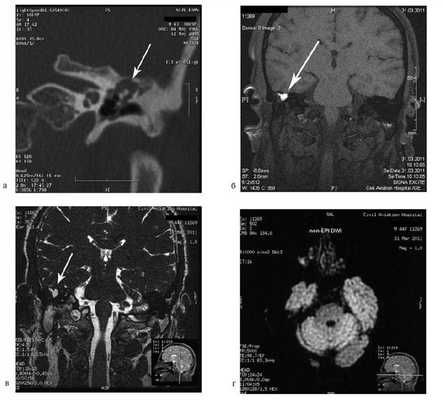

На КТ правой височной кости определяется затемнение в области аттика и антрума, цепь слуховых косточек сохранена (рис. 3, а). Рисунок 3. КТ и МРТ височных костей больного А. с адгезивным средним отитом справа, фиброзной облитерацией аттика. а — КТ; б — МРТ основания черепа в режиме Т1; в — в режиме Т2; г — в режиме non-EPI DWI.

Пациенту выполнена МРТ основания черепа по описанной методике (рис. 3, б—г).

В режиме Т1 и Т2 справа определяется очаг с высокой интенсивностью сигнала, тогда как в режиме non-EPI DWI патологических образований не выявлено. Диагноз: адгезивный средний отит справа, фиброзная облитерация аттика.